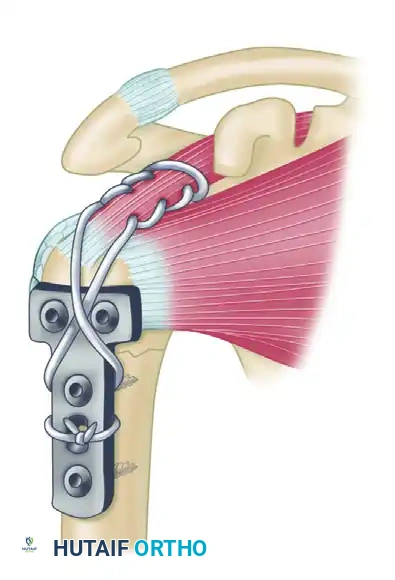

To counteract these deforming forces, Healy, Jupiter, Kristiansen, and White described a highly effective combination technique utilizing a buttress plate augmented with heavy tension band wiring.

Biomechanical Rationale:

The supraspinatus and infraspinatus exert a powerful superior and posterior pull on the greater tuberosity fragment. By weaving a heavy nonabsorbable suture through the rotator cuff tendon insertions and anchoring it directly to the plate, the surgeon neutralizes the muscular pull. This converts the distracting forces into compressive forces across the fracture site and protects the proximal metaphyseal screws from catastrophic pullout.

Step 1: Identification of the nonunion site. The proximal fragment is subjected to superior displacement by the supraspinatus, while the humeral shaft is pulled medially by the pectoralis major.

Step 2: Following debridement of the nonunion and bone grafting, a T-plate or proximal humeral locking plate is applied to the lateral aspect of the humerus to provide a rigid buttress.

Step 3: A heavy, nonabsorbable suture (e.g., #5 FiberWire) is woven through the rotator cuff utilizing a Krackow stitch configuration. The suture is then passed through the proximal holes of the plate and tied securely in a figure-of-eight fashion, effectively neutralizing the pull of the rotator cuff on the proximal fragment.